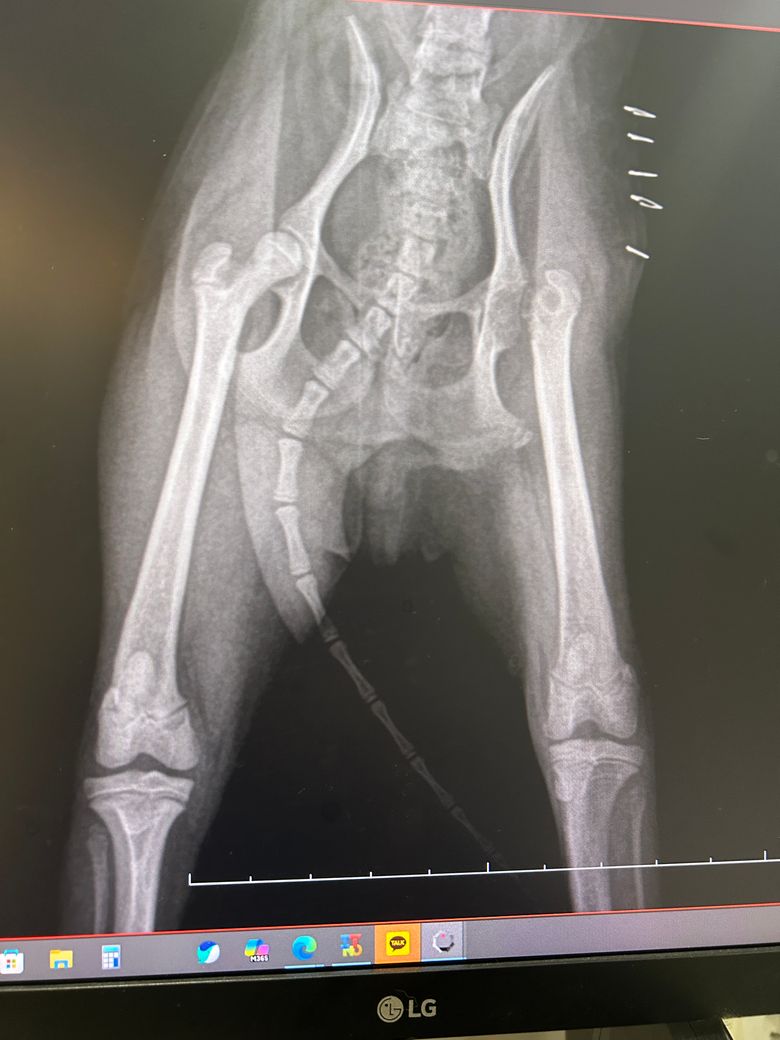

지난번 오른쪽 대퇴골두 절단술 받았습니다

엑스레이상 반대쪽도 혹시 의심 소견 있을까요?

가능성은 낮아보이지만 올려준 사진 자체가 방사선 원본이 아니라 모니터를 촬영한 사진이라 정확한 판단에 어려움이 있습니다. 그리고 시간이 지났다면 지금 현 시점 사진이 더 중요하니 방사선 재촬영을 하시기 바랍니다.